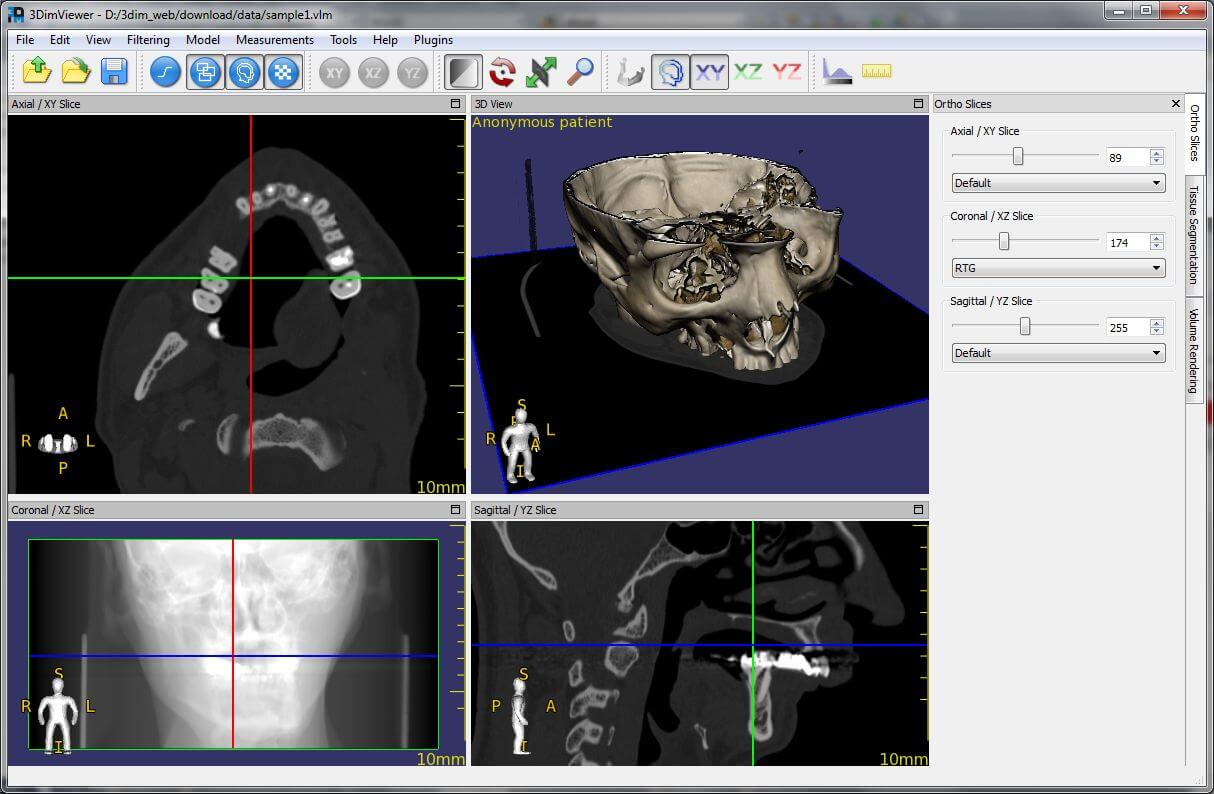

Лазерная камера для печати медицинских изображений на пленке стандарт dicom